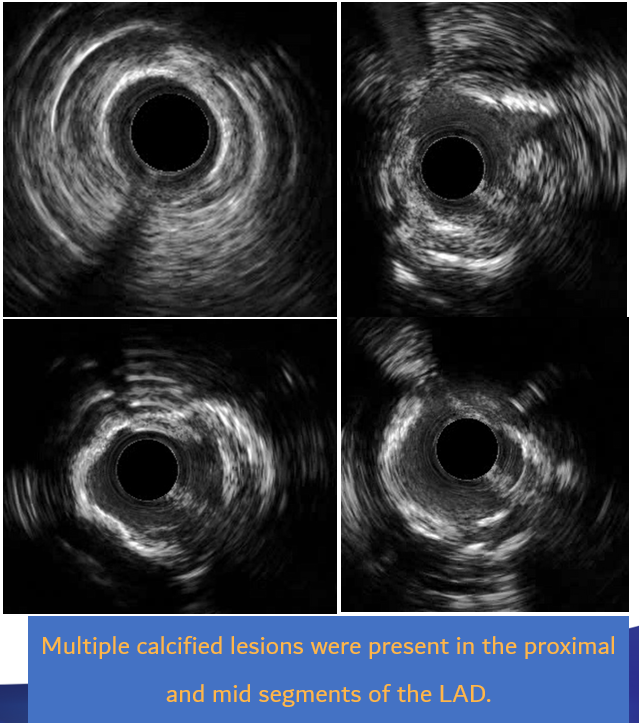

Relevant Catheterization Findings

30% stenosis in LMT; 100% stenosis in LCX£»99% stenosis with calcification in the LAD£»99% stenosis in the RCA¡£

LAD:

Neither 0.8 ¡¿ 10 mm nor 1.25 ¡¿ 15 mm balloon could cross the mid LAD lesion; tactile feedback confirmed calcification;